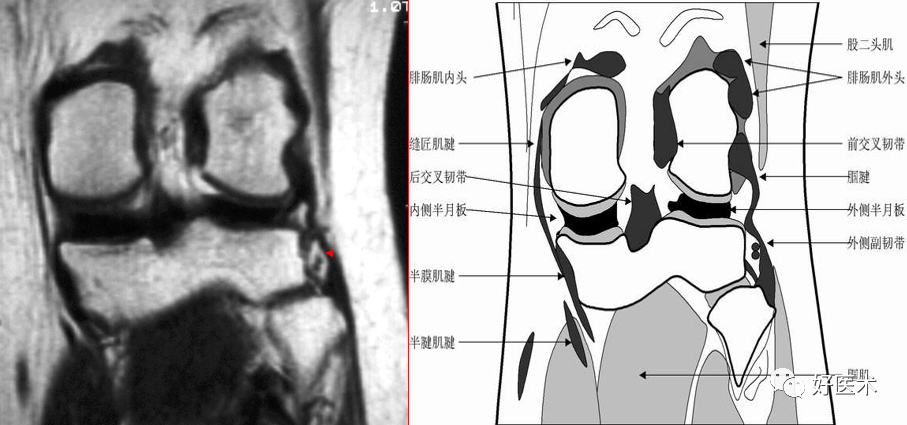

半月板的解剖与功能(戴刚).pptx

半月板的解剖与功能ppt